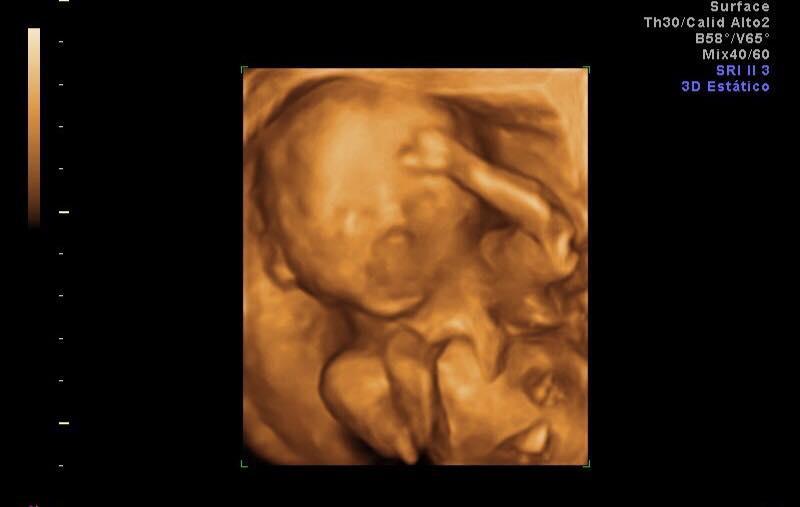

Con trai của cặp đôi sẽ chào đời vào tháng 1/2019.